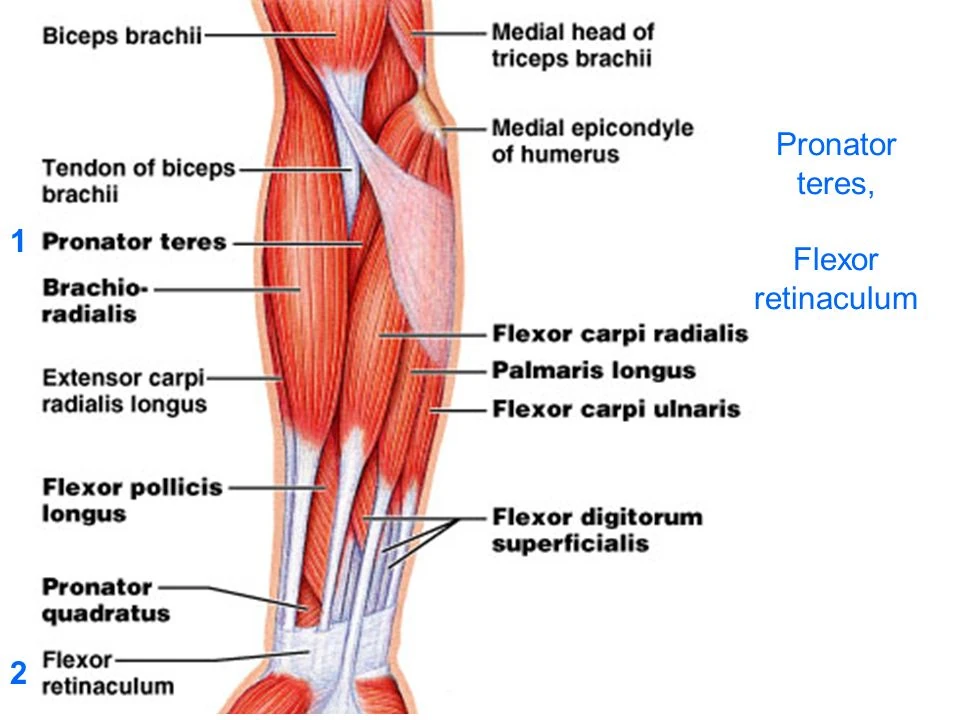

Анатомия и функции мышцы brachioradialis